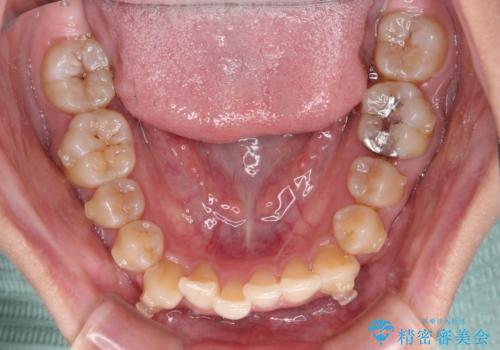

【モニター】下顎前歯のデコボコをインビザラインできれいに

下顎前歯にデコボコが集中していたため、顎間ゴムによる後方移動とIPR(歯と歯の間を削ること)により歯列を整えることとしました。

下顎前歯のデコボコが集中しており、奥歯の咬み合わせは、上顎に対して下顎が前方位にある状態でした。下顎の歯列を後方へ移動させる治療はインビザラインの得意とするところですので、1年程度で無事に治療を終えることができました。